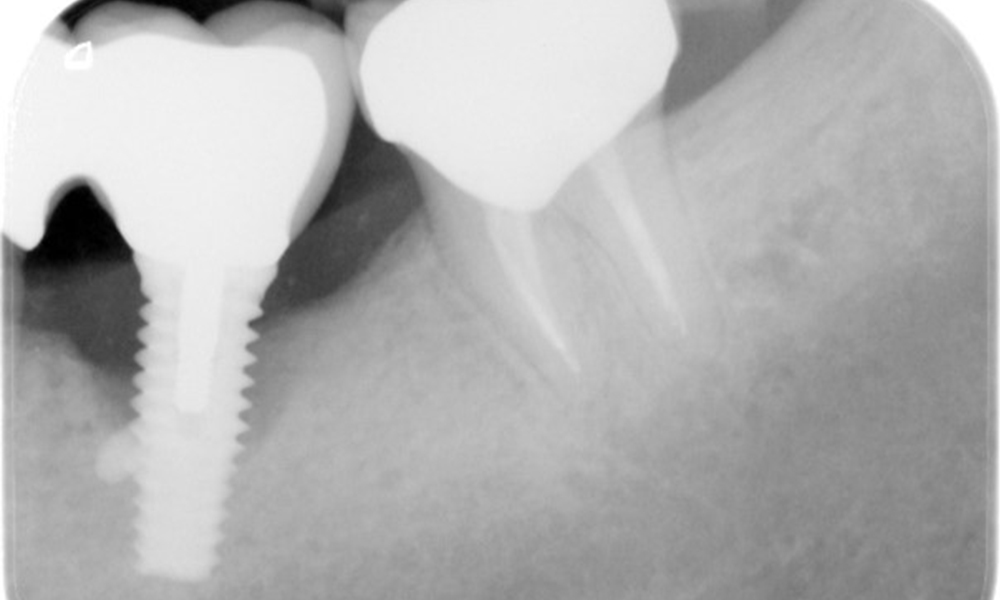

The X-ray images show the progression of bone loss.

The X-ray images show the progression of bone loss in the area of the implant in region 36: dental film from 11.02.2021 (left) and dental film from 18.01.2024 (right).